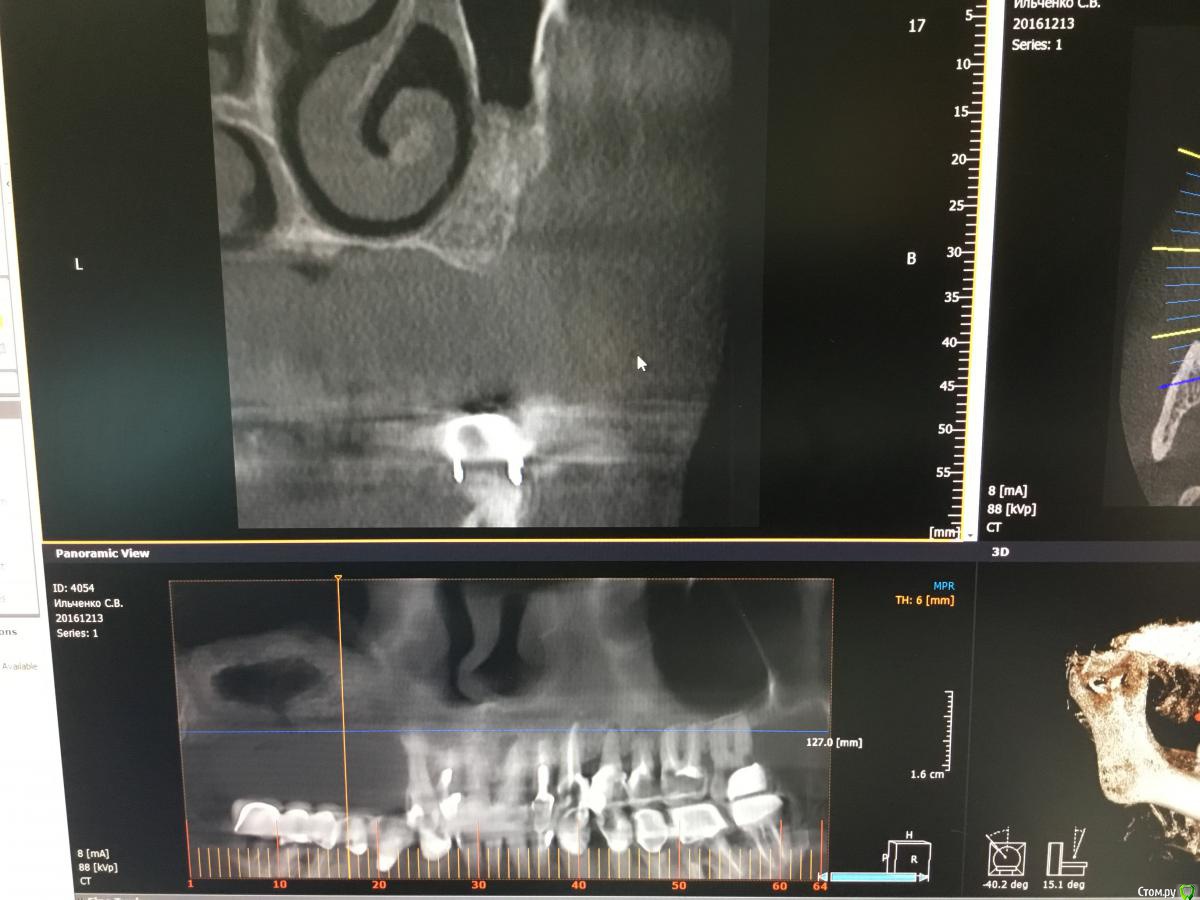

kriokov Опубликовано 17 января, 2017 Поделиться Опубликовано 17 января, 2017 Bier, Вы можете реформат панорамы залить, чтобы по позициям ясно было. Ширину увеличивали тоже? Ссылка на комментарий

Bier Опубликовано 17 января, 2017 Автор Поделиться Опубликовано 17 января, 2017 КТ на работе, ширину увеличивал в области клыковадентия 15-12, 22-25 2 Ссылка на комментарий

kriokov Опубликовано 17 января, 2017 Поделиться Опубликовано 17 января, 2017 (изменено) КТ на работе, ширину увеличивал в области клыков адентия 15-12, 22-25как думаете, почему не весь графт отработал? На установке болтов окно после синуса "окостенелое" было? Изменено 17 января, 2017 пользователем kriokov Ссылка на комментарий

Bier Опубликовано 17 января, 2017 Автор Поделиться Опубликовано 17 января, 2017 как думаете, почему не весь графт отработал? На установке болтов окно после синуса "окостенелое" было?потому что произошла неполная отслойка слизистой пазухи во время операции. Она подвернулась или расслоилась. 1 Ссылка на комментарий